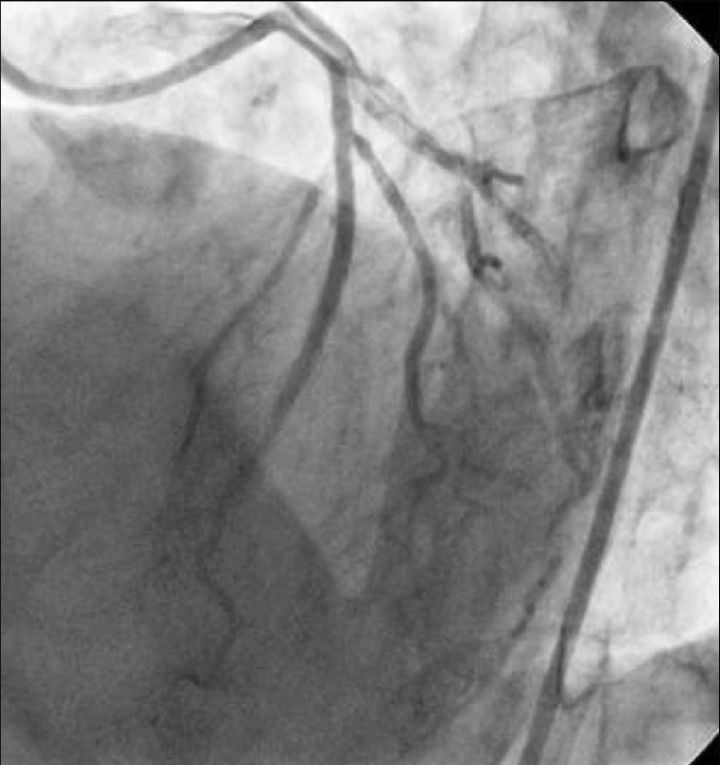

Right Coronary Artery (RCA): Dominance right. Large caliber, no significant stenosis. Angiographically normal with TIMI 3 flow. Left Main (LM): On first contrast injection afterJL engagement, mild ostial contrast staining was observed. On the second injection, there was more pronounced staining with dye hang-up, consistentwith catheter-induced LM dissection with suspectedpropagation toward the LAD/LCX.

- Actions: Stopped contrast injections; converted to RFA for stronger guide backup. Wired LAD and LCX in true lumen (confirmed by IVUS).

- Stenting: LM ¡æ LAD drug-eluting stent (DES) to seal LM entry; mini-TAP to LCX for ostial coverage.

- Imaging: IVUS pre-PCI confirmed dissection/intimal flap with intramural hematoma extending into proximal LAD/LCX; post-PCI showed good expansion/apposition, no residual entry.

- Final result: TIMI 3 flow in LAD and LCX; LM sealed; no residual flow-limiting dissection.